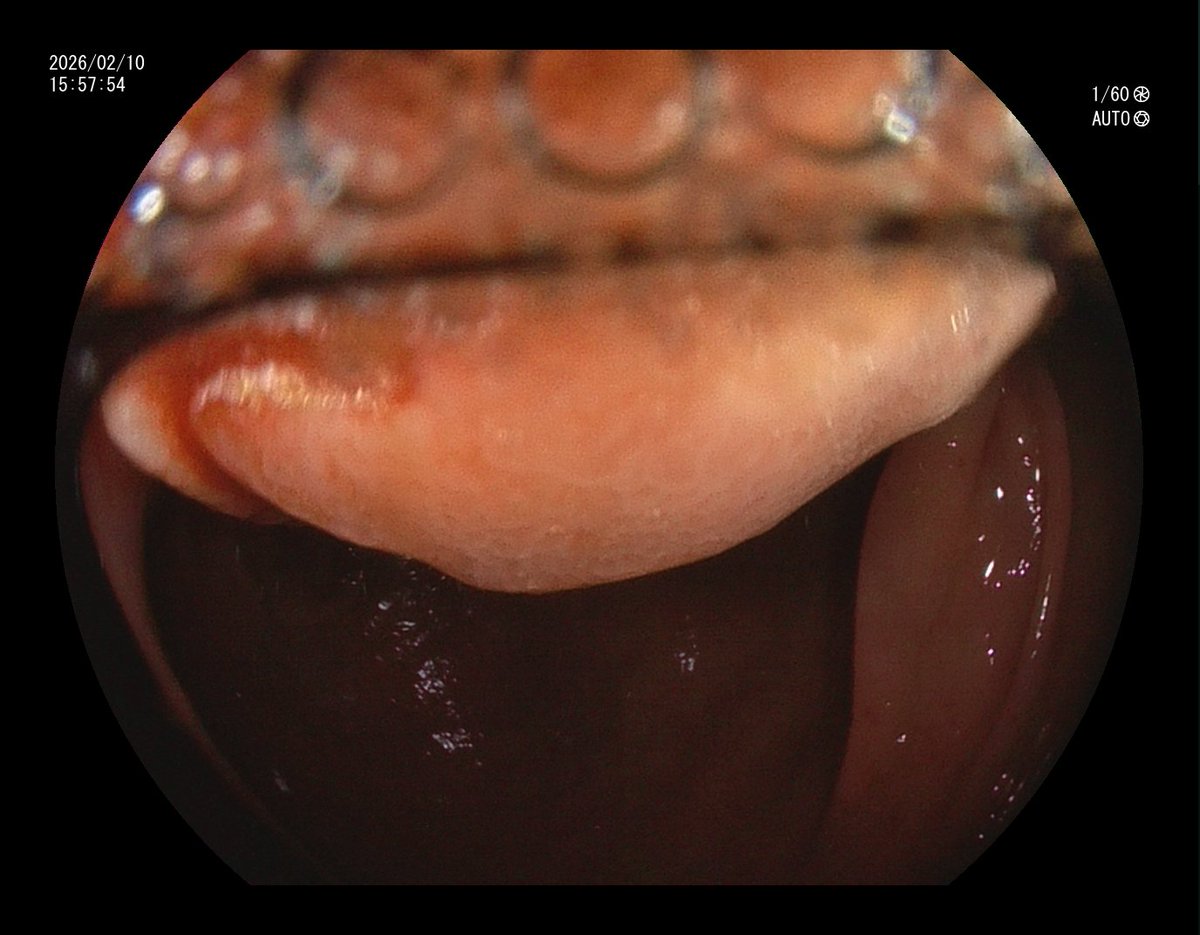

1. Antrum, low grade dysplasia. Removed via ESD. Specimen 43x32mm / dysplasia 20x13mm. R0